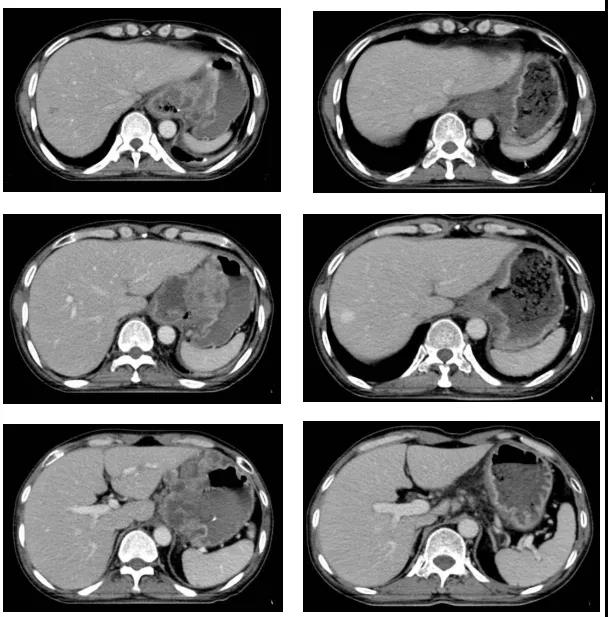

免疫治疗药物在食管癌二线甚至一线治疗中已经取得了令人振奋的临床疗效,人们也期待着其在新辅助治疗方面能够同样带来惊喜!本期我们将分享一例IVA期食管癌通过术前新辅助...

免疫治疗药物在食管癌二线甚至一线治疗中已经取得了令人振奋的临床疗效,人们也期待着其在新辅助治疗方面能够同样带来惊喜!本期我们将分享一例IVA期食管癌通过术前新辅助...